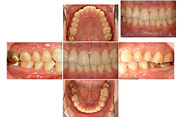

【口腔内写真】

口の中の写真撮影は、現在の状況や治療の効果、病状の進行をしっかりと把握し、問題点を見逃さないためにとても重要です。撮影した画像は、右のような説明用資料としても使用します。